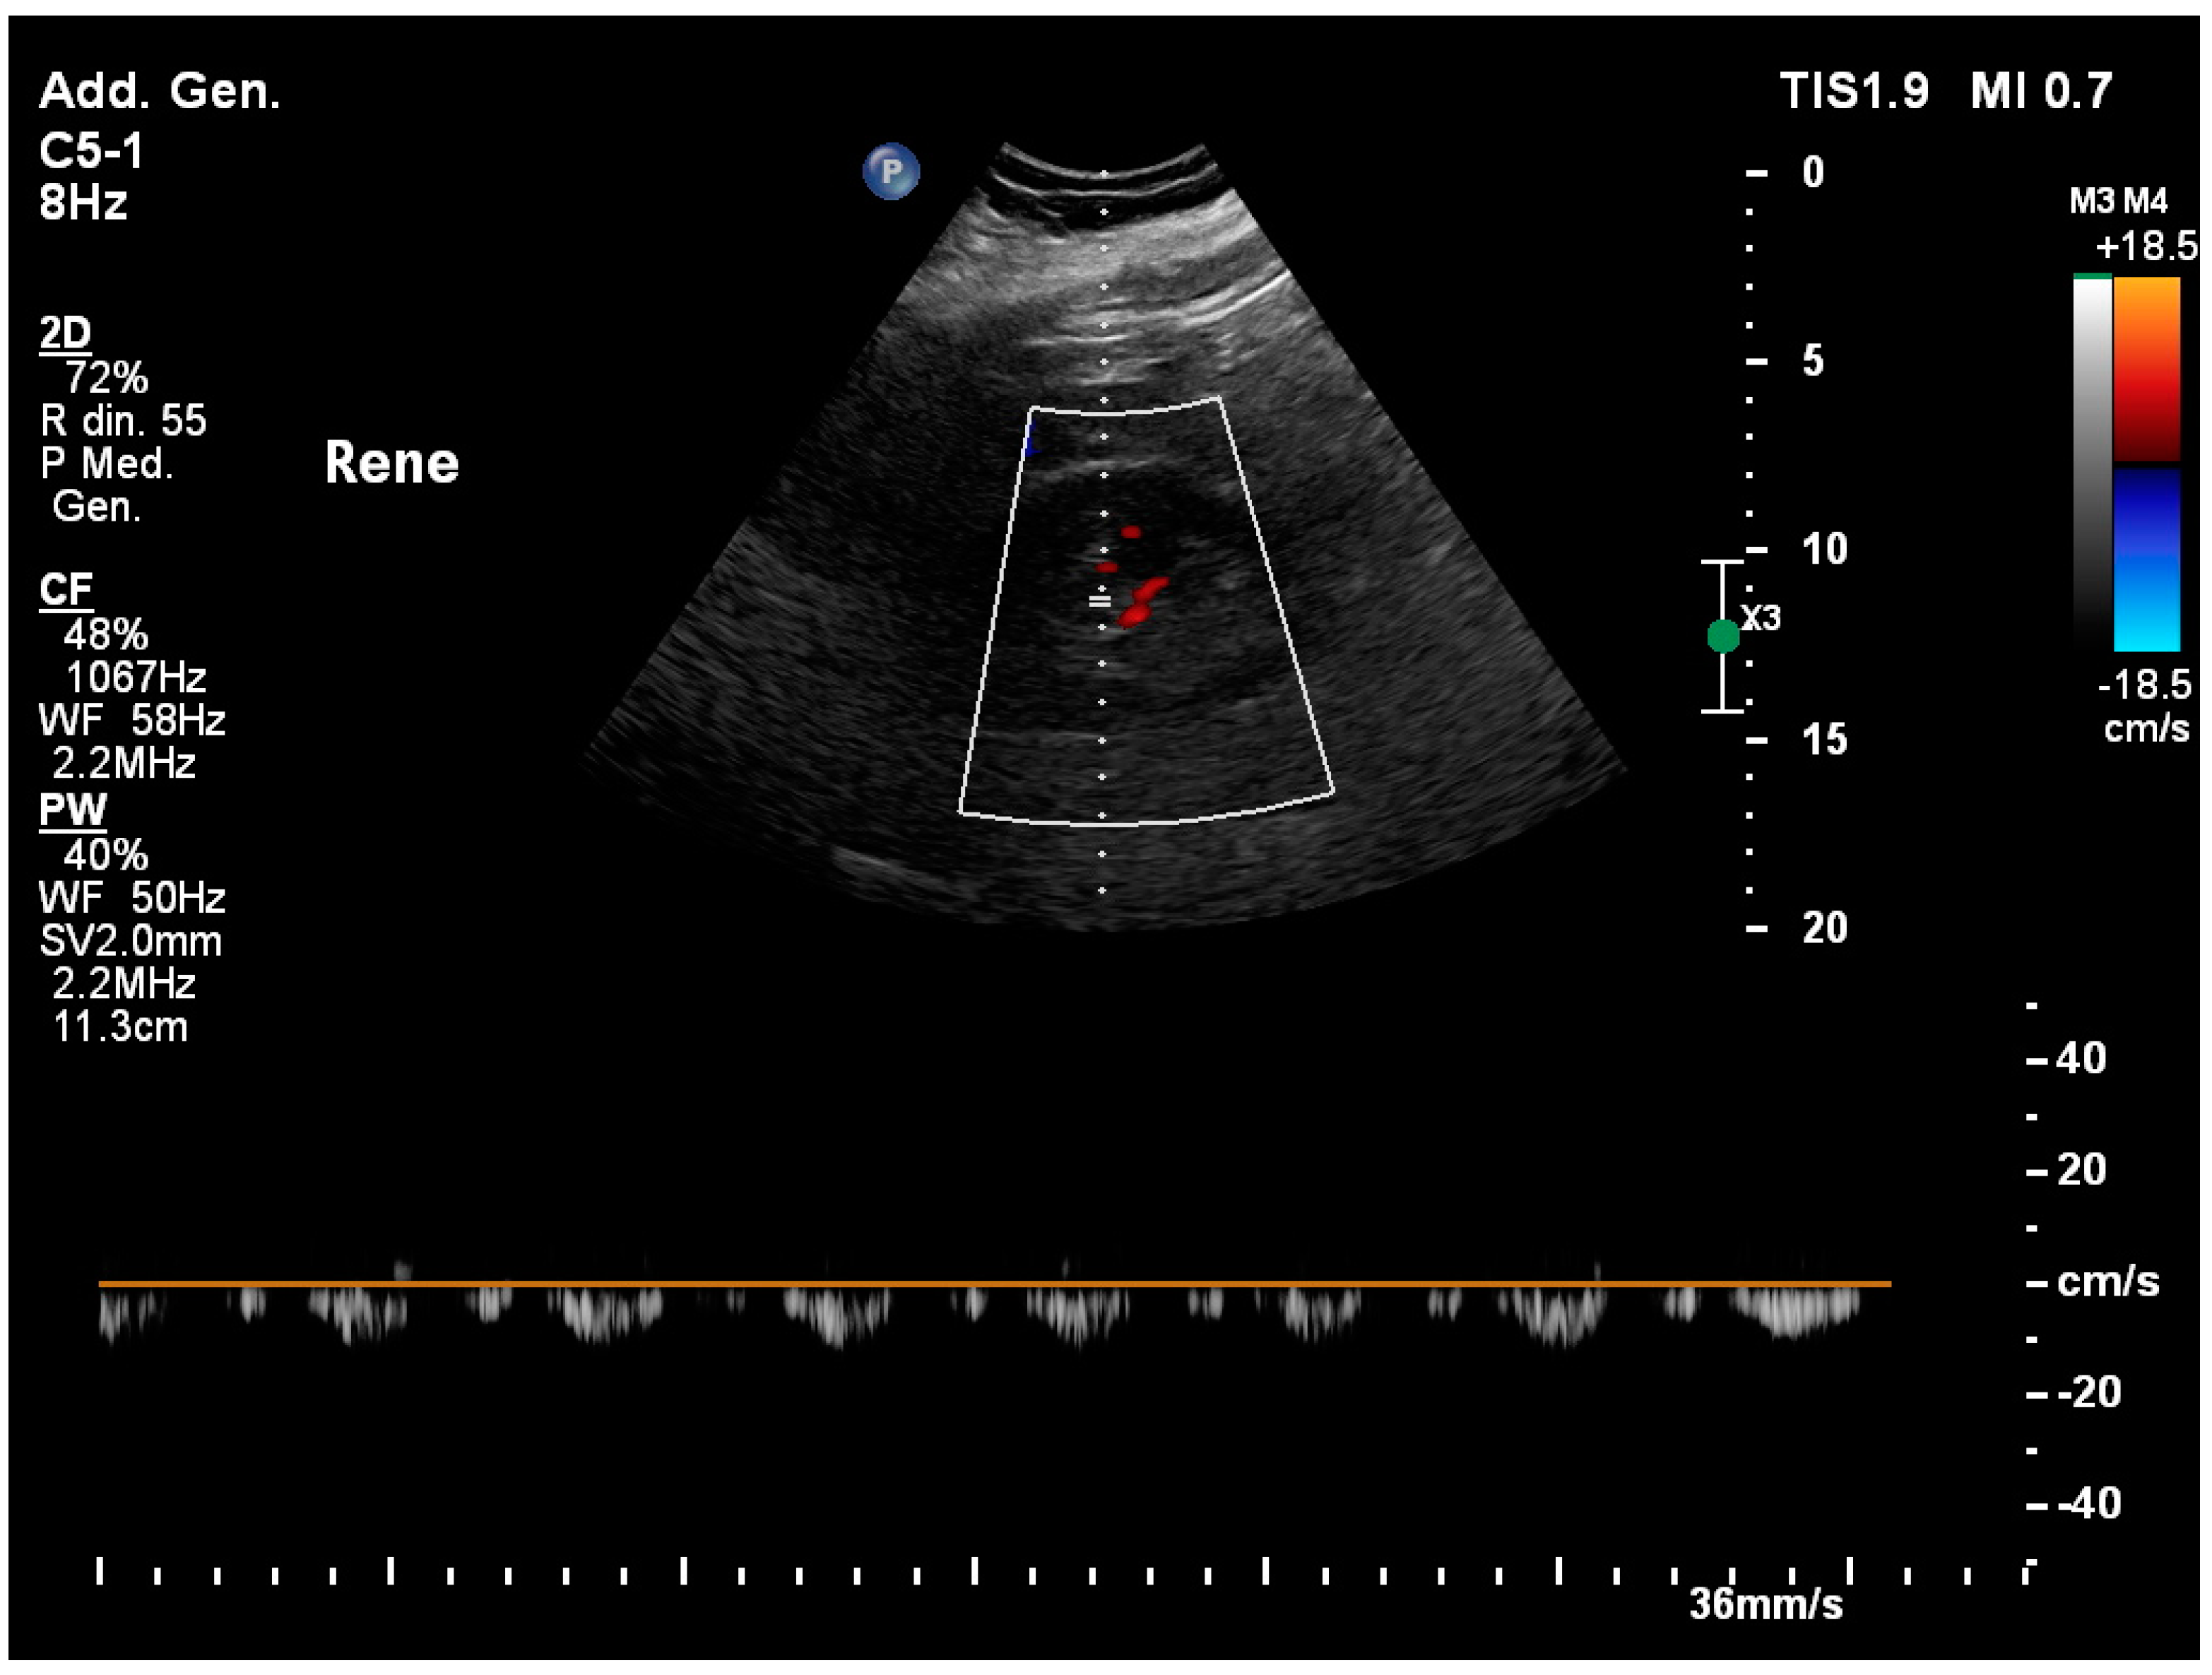

3.7. Identification of the Ureteral Jet